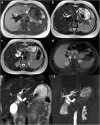

Objectives: We aim to illustrate the multimodal imaging spectrum of hepatic involvement in tuberculosis (TB). Whilst disseminated tuberculosis on imaging typically manifests as multiple small nodular lesions scattered in the liver parenchyma, isolated hepatic tuberculosis remains a rare and intriguing entity.

Methods: Indubitably, imaging is the mainstay for detection of tubercular hepatic lesions which display a broad spectrum of imaging manifestations on different modalities. While sonography and computed tomography (CT) findings have been described in some detail, there is a paucity of literature on magnetic resonance imaging (MRI) features. Due to a significant overlap with other commoner and similar appearing hepatic lesions, hepatic tuberculosis is often either misdiagnosed or labelled as indeterminate lesions. This article is a compendium of cases highlighting the spectrum of imaging patterns that can be encountered in patients with isolated primary hepatic tuberculosis as well as disseminated (secondary) disease. Rare patterns of primary disease such as tubercular cholangitis, hypervascular liver masses, and those with vascular complications are also illustrated and discussed.

Teaching points: • Hepatic TB has myriad imaging manifestations and is often confounded with neoplastic lesions. • Imaging patterns include miliary TB, macronodular TB, serohepatic TB and tubercular cholangitis. • Concurrent splenic, nodal or pulmonary involvements are helpful pointers towards the diagnosis. • Miliary calcifications along the bile ducts are characteristic of tubercular cholangitis. • Histological/microbiological confirmation is often necessary to confirm the diagnosis.